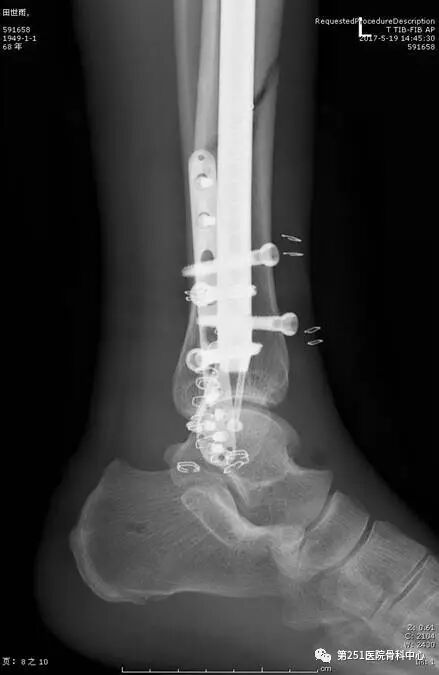

病例9:男性、68岁、车祸伤,胫腓骨远端骨折。